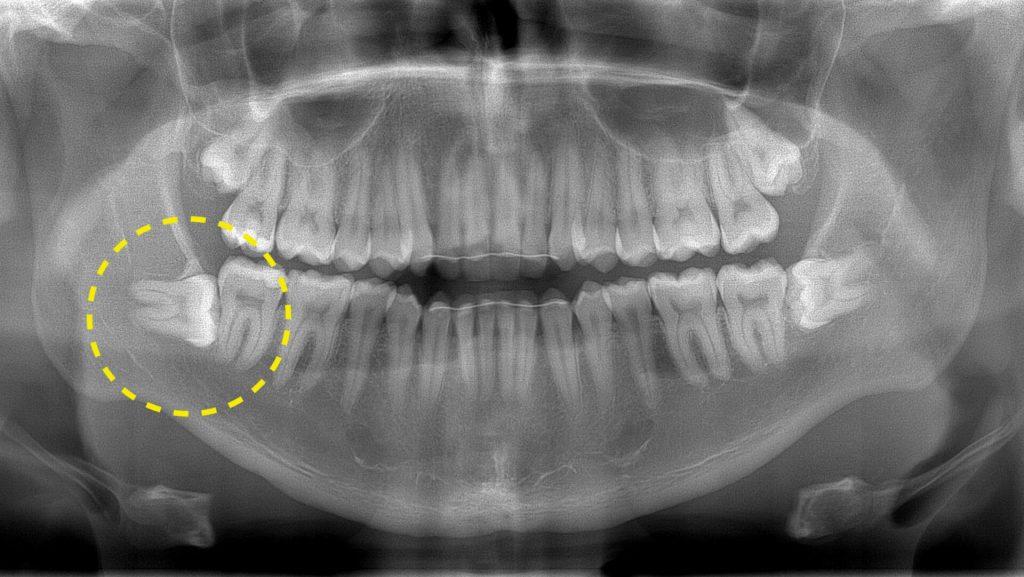

Длительность заживления зависит от сложности операции: простой, сложной или атипичной (например, когда зуб мудрости был расположен в челюсти под углом, и его пришлось удалять прямо из кости). Однако, в итоге все зависит от внимания пациента к собственному состоянию, и следования рекомендациям хирурга-стоматолога из клиники Осадчего.